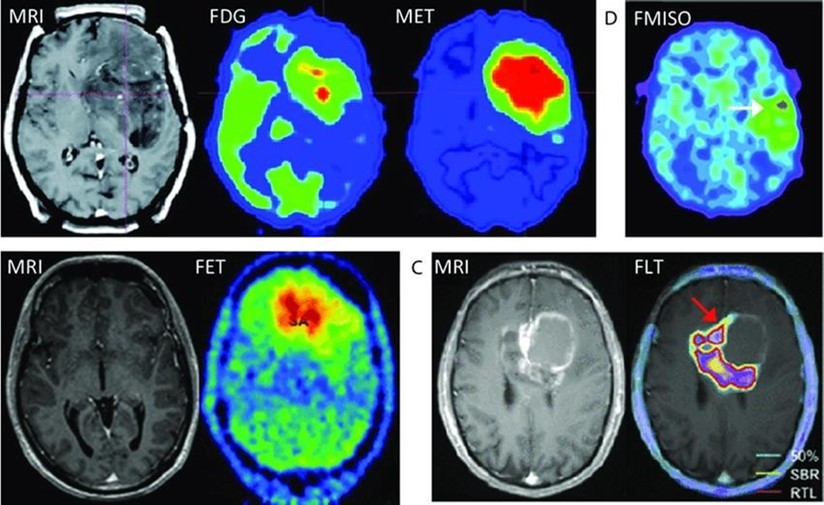

It is a non–invasive method. It can be used to monitor the chemical changes of tissues. We can simultaneously evaluate several metabolites. Two examples of where MRS is very helpful in the brain: The invasion of the tumor (Glioblastoma multiform (GBM) into the surrounding tissues, which is not clear in normal T2 images, but can be determined by MRS. By MRS, it is possible to distinguish two types of lesions that look similar to each other in normal MRI images (such as tumor recurrence and tumor necrosis after radiotherapy). MRS imaging has found wide applications in the field of cancer diagnosis. Among the fields of clinical application of MRS, we can mention the diagnosis (between normal and cancerous tissue, different types of cancer and neoplastic from non–neoplastic), designing the best treatment regimens for each patient, and monitoring the patient after treatment. MRS in tumors: In brain tumors, spectroscopy can determine the degree of malignancy. As malignancy increases, NAA and creatine decrease and choline, lactate and fat increase. Fat is seen in the necrotic parts of the tumor. Lactate concentration increases in rapidly growing tumors due to anaerobic glycolysis. Diagnosing tumor recurrence from the effects of radiotherapy: Increased choline is a marker for tumor recurrence. Changes due to radiotherapy usually decrease NAA, creatine and choline. If necrosis has occurred as a result of radiotherapy, fat and lactate can also be seen in the spectrum. Molecular imaging using spectroscopy Cerebral ischemia and infarction: When the brain suffers from ischemia, anaerobic respiration of glucose is used and lactate increases. Choline increases and NAA and creatine decrease. If it happens after ischemia, the fat signal is also seen. trauma: It is a useful method to assess the degree of nerve damage and predict the results. The clinical consequences are opposite to the NAA/Cr ratio, and the observation of lactate and fat indicates the seriousness of the condition. infectious diseases: decrease naa Inside the abscess, lactate, alanine, cytosolic acid and acetate increase. Alzheimer: In the advanced stages of Alzheimer's, NAA decreases and myo–inositol increases. MS: The increase of choline and lactate has shown that the increase of choline can be due to the increase of phospholipid as a result of breaking the myelin of the cell and the increase of lactate is due to the increase of the anaerobic respiration of the cell due to the increase of the cell metabolism. In addition, there is evidence of increased lipids, and most importantly, decreased NAA, which is caused by nerve damage. And recently, it has been found that glutamate and myoinositol levels increase in acute MS lesions. Parkinson: In most studies in Parkinson's disease, no changes in metabolites have been observed, only when Parkinson's has caused brain atrophy, a decrease in NAA in the basal ganglia has been observed (Figure 3, Figure 4, Figure 5, Figure 6).